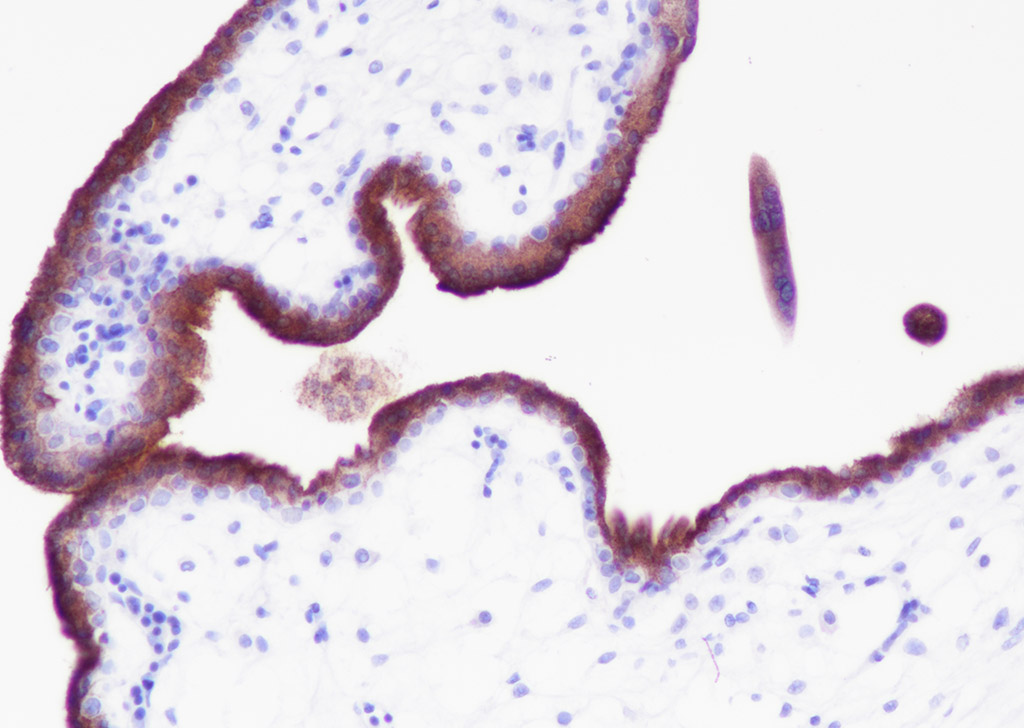

Tissue: Human placenta Section type: Formalin fixed & Paraffin -embedded section Retrieval method: High temperature and high pressure Retrieval buffer: Tris/EDTA buffer, pH 9.0 Primary ab dilution: 1:1000 Primary ab incubation condition: 1 hour at room temperature Counter stain: Hematoxylin Comment: Color brown is the positive signal for bsm-60327R

Tissue: Human tonsil Section type: Formalin fixed & Paraffin -embedded section Retrieval method: High temperature and high pressure Retrieval buffer: Tris/EDTA buffer, pH 9.0 Primary ab dilution: 1:100 Primary incubation condition: 1 hour at room temperature Counter stain: Hematoxylin Comment: Color brown is the positive signal for bsm-60327R